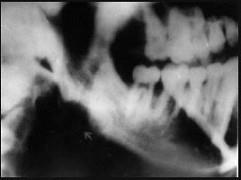

问题 常引起边缘性骨髓炎的间隙感染是 ( )

选项 A.颊间隙 B.咬肌间隙 C.颏下间隙 D.颌下间隙 E.眶下颊间隙

答案 B